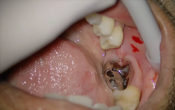

Collection privée du Docteur COMMISSIONNAT